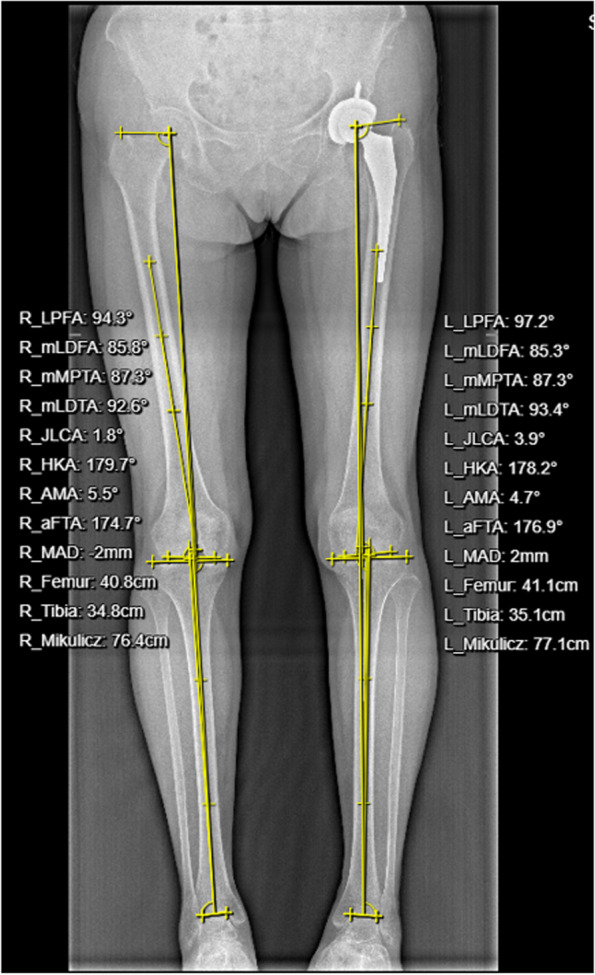

Methods: Collected were data from 350 patients who underwent direct anterior hip arthroplasty between 2008 and 2013, including demographic information, imaging data, Harris hip scores, and surgical complications. Variables, measured radiographically or by CT, included hip offset, leg length discrepancy, component position, and stability within one week after surgery and at the last follow-up. The data were subjected to statistical analysis by using paired t-tests and Pearson chi-square tests.

Results: Data were harvested by follow-up and self-reported questionnaires. The postoperative follow-up lasted for 13.1 years on average (minimum, 10 years; maximum, 15 years), and the overall survival rate of hip prostheses was 96.3%. The mean Harris score at the final follow-up was 91.8 points. After excluding patients with significant preoperative hip deformities, the incidence of postoperative limb inequality (> 5 mm) was 4.9% at the last follow-up, and the incidence of hip offset discrepancy (> 5 mm) was 14.6%. The overall proportion of the acetabular components located in the Lewinnek safe zone was 77.7%, whereas the proportion of femoral prostheses in the safe zone (< 3° inclination) was 94.0%. Based on the revised data and the last follow-up imaging, the total proportion of acetabular and femoral prostheses with a radiolucence of > 2 mm was 5.1%.